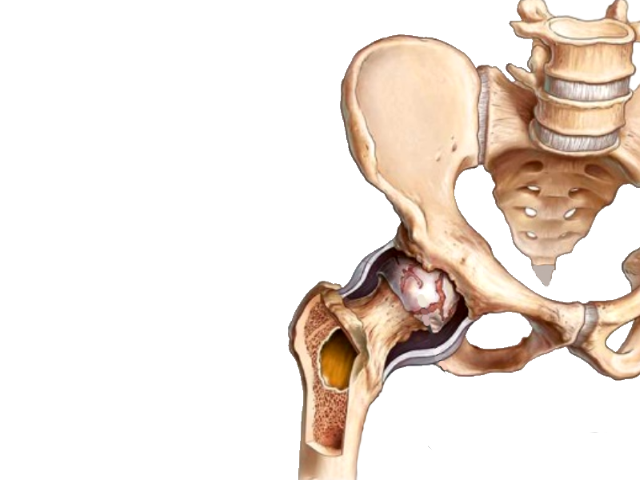

Остеоартрит фасеточных суставов: медицинские снимки и схемы